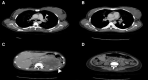

Case summary: Thirty-four-year-old woman with the unremarkable medical history presented with epigastric pain and dyspnoea. Electrocardiogram showed ST-segment elevation in the inferior limb leads. She underwent an emergency coronary angiogram, which showed a high thrombus burden in the distal right coronary artery. A subsequent echocardiogram demonstrated a 31 × 33 mm right atrial mass adhering to the inferior vena cava and abdominal computed tomography (CT) scan revealed a 113 × 85 mm necrotic mass in the left adrenal bed, with tumour thrombus extending proximally to the confluence of hepatic veins immediately inferior to the right atrium and distally to iliac vein bifurcation. Blood parameters, thrombophilia panel, vanillylmandelic acid, 5 hydroxy indole acetic acid, and homovanillic acid levels were normal. Tissue sampling confirmed the diagnosis of PHEOs. The surgical procedure was not planned due to the presence of metastatic foci on imaging, including positron emission tomography (PET)-CT. Anticoagulation with rivaroxaban and treatment with 177Lu-DOTATATE-based peptide receptor radionuclide therapy (PRRT) was initiated.